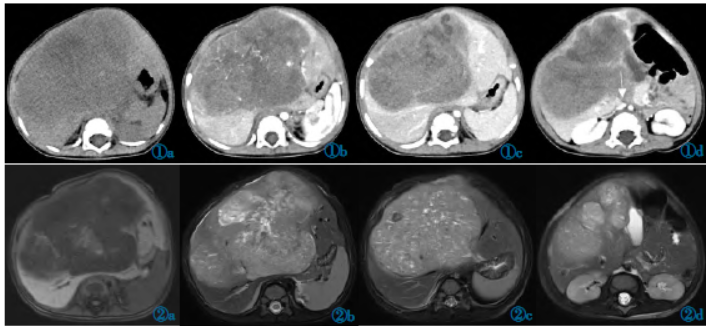

1 周”入院。专科检查,肝区可触及10 cm×10 cm 包块,质硬,边界清,轮廓不规则。CT 平扫示肝左叶内侧段见一巨大稍低密度肿块,大小约13 cm×9.2 cm×12 cm,CT 值约21~35 HU,肠管受压向左移位(图1a)。

经静脉注入碘海醇

增强扫描:动脉期肿块呈不均质轻度强化,CT 值约为54 HU,肿块内低密度区无强化(图1b),门脉期CT 值约为45 HU,可见肝内血管受压推移、下腔静脉受压(图1c,1d),延迟期CT 值约为38 HU。MRI 示肝左叶见一巨大软组织肿块影突出于肝轮廓外,T1WI 呈低信号(图2a),T2WI 压脂呈高信号,其内信号不均匀,夹杂少许T2WI 高信号和低信号(图2b,2c),胆囊向左移位(图2d)。

图1 肝脏横纹肌样瘤CT 图。图1a:CT 平扫示肝左叶内侧段见一巨大稍低密度肿块;图1b:增强扫描动脉期示肿块呈不均质轻度强化;图1c,1d:增强扫描门脉期示肝内血管受压推移、下腔静脉受压。图2 肝脏横纹肌样瘤MRI 图。图2a:T1WI 示肿块整体呈低信号;图2b,2c:T2WI 压脂示肿块整体呈高信号,夹杂高信号和低信号;图2d:T2WI 压脂示胆囊向左移位。图3 肝脏横纹肌样瘤病理图。光镜见异型细胞弥漫分布,核大,呈圆形或梭形,包浆透亮,部分胞浆丰富,嗜酸性,可见核分裂象(HE)。